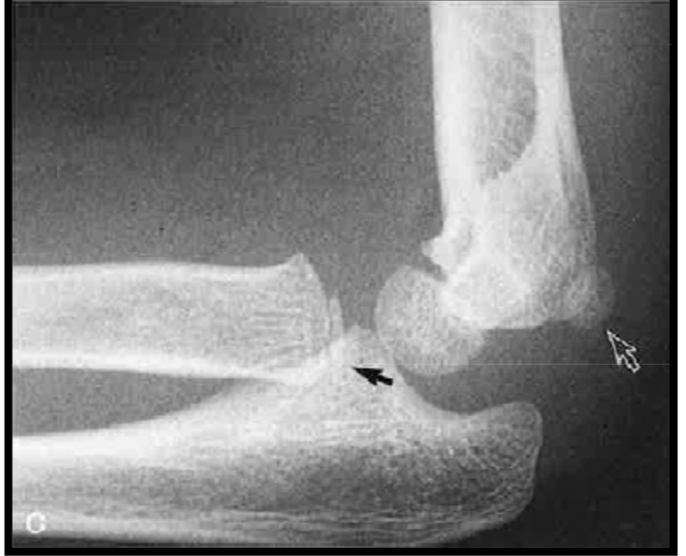

Maturation osseuse – Vues de profil

varaition anat normal

variation normal